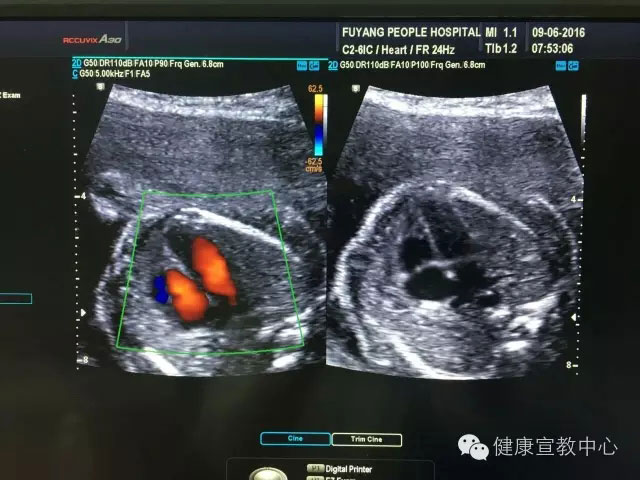

(胎兒中孕篩查)

(胎兒超聲心動(dòng)圖)